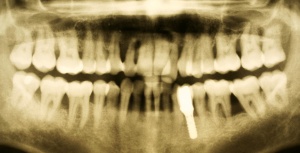

[Abb-2]In den vergangenen zehn Jahren wurden circa 34.000 Implantate durch das SanABw bzw. das KdoSanDst UA III genehmigt. Wenn die von Roos-Jansacker publizierte Prävalenzrate von 6,6 % zugrunde gelegt wird, müsste zwischenzeitlich an circa 2250 Implantaten eine Periimplantitis diagnostiziert worden sein. Zitzmann et al. geben eine Rate von 28 % periimplantäre Entzündungen an. Dies bedeutet, dass circa 9500 Implantate eine Mukositis bzw. Periimplantitis aufwiesen bzw. aufweisen.